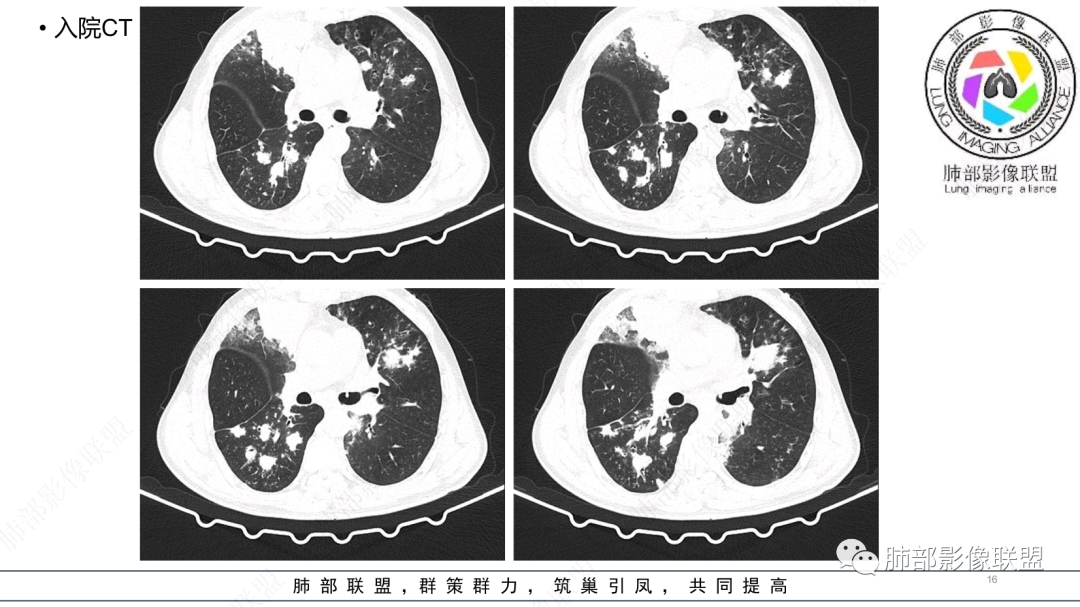

中老年男性,发病一周,发热,炎症指标明显增高,双肺支气管扩张基础,双肺可见多发结节、斑片状、团块状密度增高,边缘尚清。病灶分布与支气管关系密切,考虑支扩合并感染,铜绿,NTM、奴卡、曲霉等,环卫工人,可能接触腐败物较多,考虑曲霉可能大,鉴别奴卡。

男性,56岁,清洁工,临床表现咳嗽咳痰发热。胸部影像:两肺散在斑片、结节及实变影,大部分沿气道分布,以下肺为著并伴发多发支气管扩张及囊腔影,实验室检查白细胞增高,考虑感染性病变,曲霉、铜绿及NTM。

56岁,工作性质:环卫工人。主诉:咳、痰、喘、发病一周。急性起病(或者慢病+AE),呼吸道感染症状。化验指标白细胞、中性、CRP明显升高。影像学显示多灶性,有柱状支扩,囊状支扩等结构肺病,责任细菌主要考虑铜绿假单胞菌,不排除合并其他细菌以阴杆为主;存在树芽影,发热,炎症沿支气管束分布,是否合并TB?真菌?;树芽伴发热支原体感染也要需要考虑进去;全肺多灶性炎症,部分病灶周围有晕,右上叶疑似反晕,内部疑似有丝,右下肺考虑存在粘液栓,加之环卫工工作性质,考虑霉菌,主要考虑曲霉。

两肺支扩,两肺沿支气管分布多发结节、树芽及团块,边缘模糊,部分支气管管壁增厚,考虑气道侵袭性曲霉菌,鉴别铜绿、奴卡、结核。

多发结节,部分结节边缘清楚,部分边缘模糊,支扩合并肉芽肿性炎,奴卡菌与曲霉之间选择。

CT:双肺延支气管血管束分布斑片状、团块状、树芽状密度增高影,部分边界模糊,支气管扩张、部分管壁增厚。考虑气道吸入细菌性感染,铜绿假单孢?